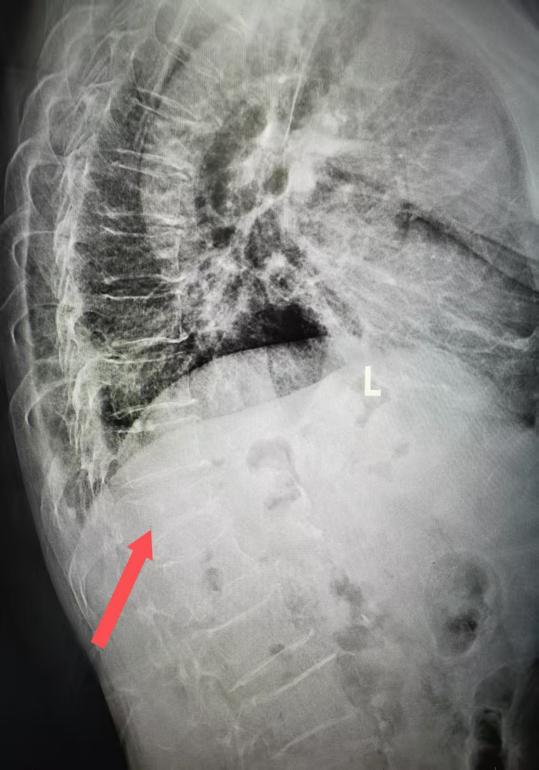

第1椎腰压缩骨折正位x线片、侧位x线片(箭头所示)